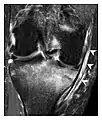

a

b

Figure 13: Partial osseous avulsion of the gluteal muscles at the greater trochanter in a 59-year-old man who presented with the right hip pain without a history of trauma. Lauenstein view and anteroposterior and radiographs (not shown) did not show an obvious fracture line or disruption of bony contours in the acetabulum or the right femoral neck. (a) Coronal T1-weighted MRI displays an incomplete fracture line extending partially from the greater trochanter (arrow). (b) Coronal short tau inversion recovery MRI shows heterogeneous hyperintensity in the same region (arrow) as well as hyperintensity within the gluteus medius and minimus muscles (arrowheads) consistent with tissue edema and hematoma.[1]